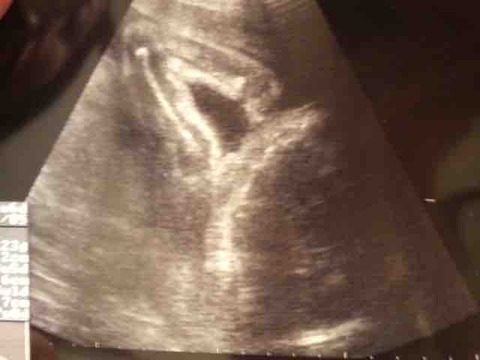

不妊治療の末に授かった息子。

お腹の中の息子は、ガッツポーズをしていましたが、

壮絶な妊婦生活を過ごし、